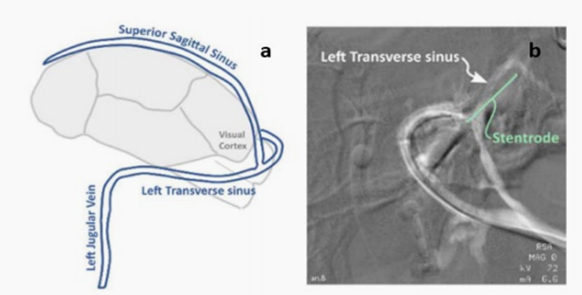

支架电极已成为脑电极领域的一种很有前途的选择。支架的直径极小,可以进入血管而不影响血液循环。通过固定支架结构上的电极点,可以收集信号或在大脑深处进行电刺激。这提供了一种相对非侵入性的方法来获取和操作神经活动。图1显示了x射线下支架电极的形态和体内状态。

图 1 支架在绵羊上矢状窦(SSS)中的部署的x线图像

Mahoney等人使用支架电极阵列、硬膜下电极阵列和头皮下电极来记录绵羊的大脑信号。血管内支架电极,由四个安装在镍钛(NiTi)上的铂电极组成支架,经静脉植入横窦。

横窦和支架电极在横窦中的位置示意图如图4所示。频闪灯被放置在距离动物右眼约20厘米处的地方,并被设置为以1.02 Hz的频率闪烁。支架电极和头皮下电极同时记录了5分钟的受刺激和未受刺激的活动。结果表明,支架和头皮电极都能成功地采集数据,每个通道都能捕获清晰的视觉诱发电位。平均而言,头皮下电极的视觉诱发电位幅度比支架电极高69%。然而,支架电极显示出更高的光谱功率,包括在噪声频带内。综合数据显示,头皮下电极的振幅和信噪比较高,可能是由于植入时间短,阻碍了支架电极完全整合到血管壁,导致定位不精确。然而,研究结果证明了使用血管内支架电极采集信号的可行性。

图4 (a)横窦的示意图 (b)x线图像显示导管在左侧横窦内的组装